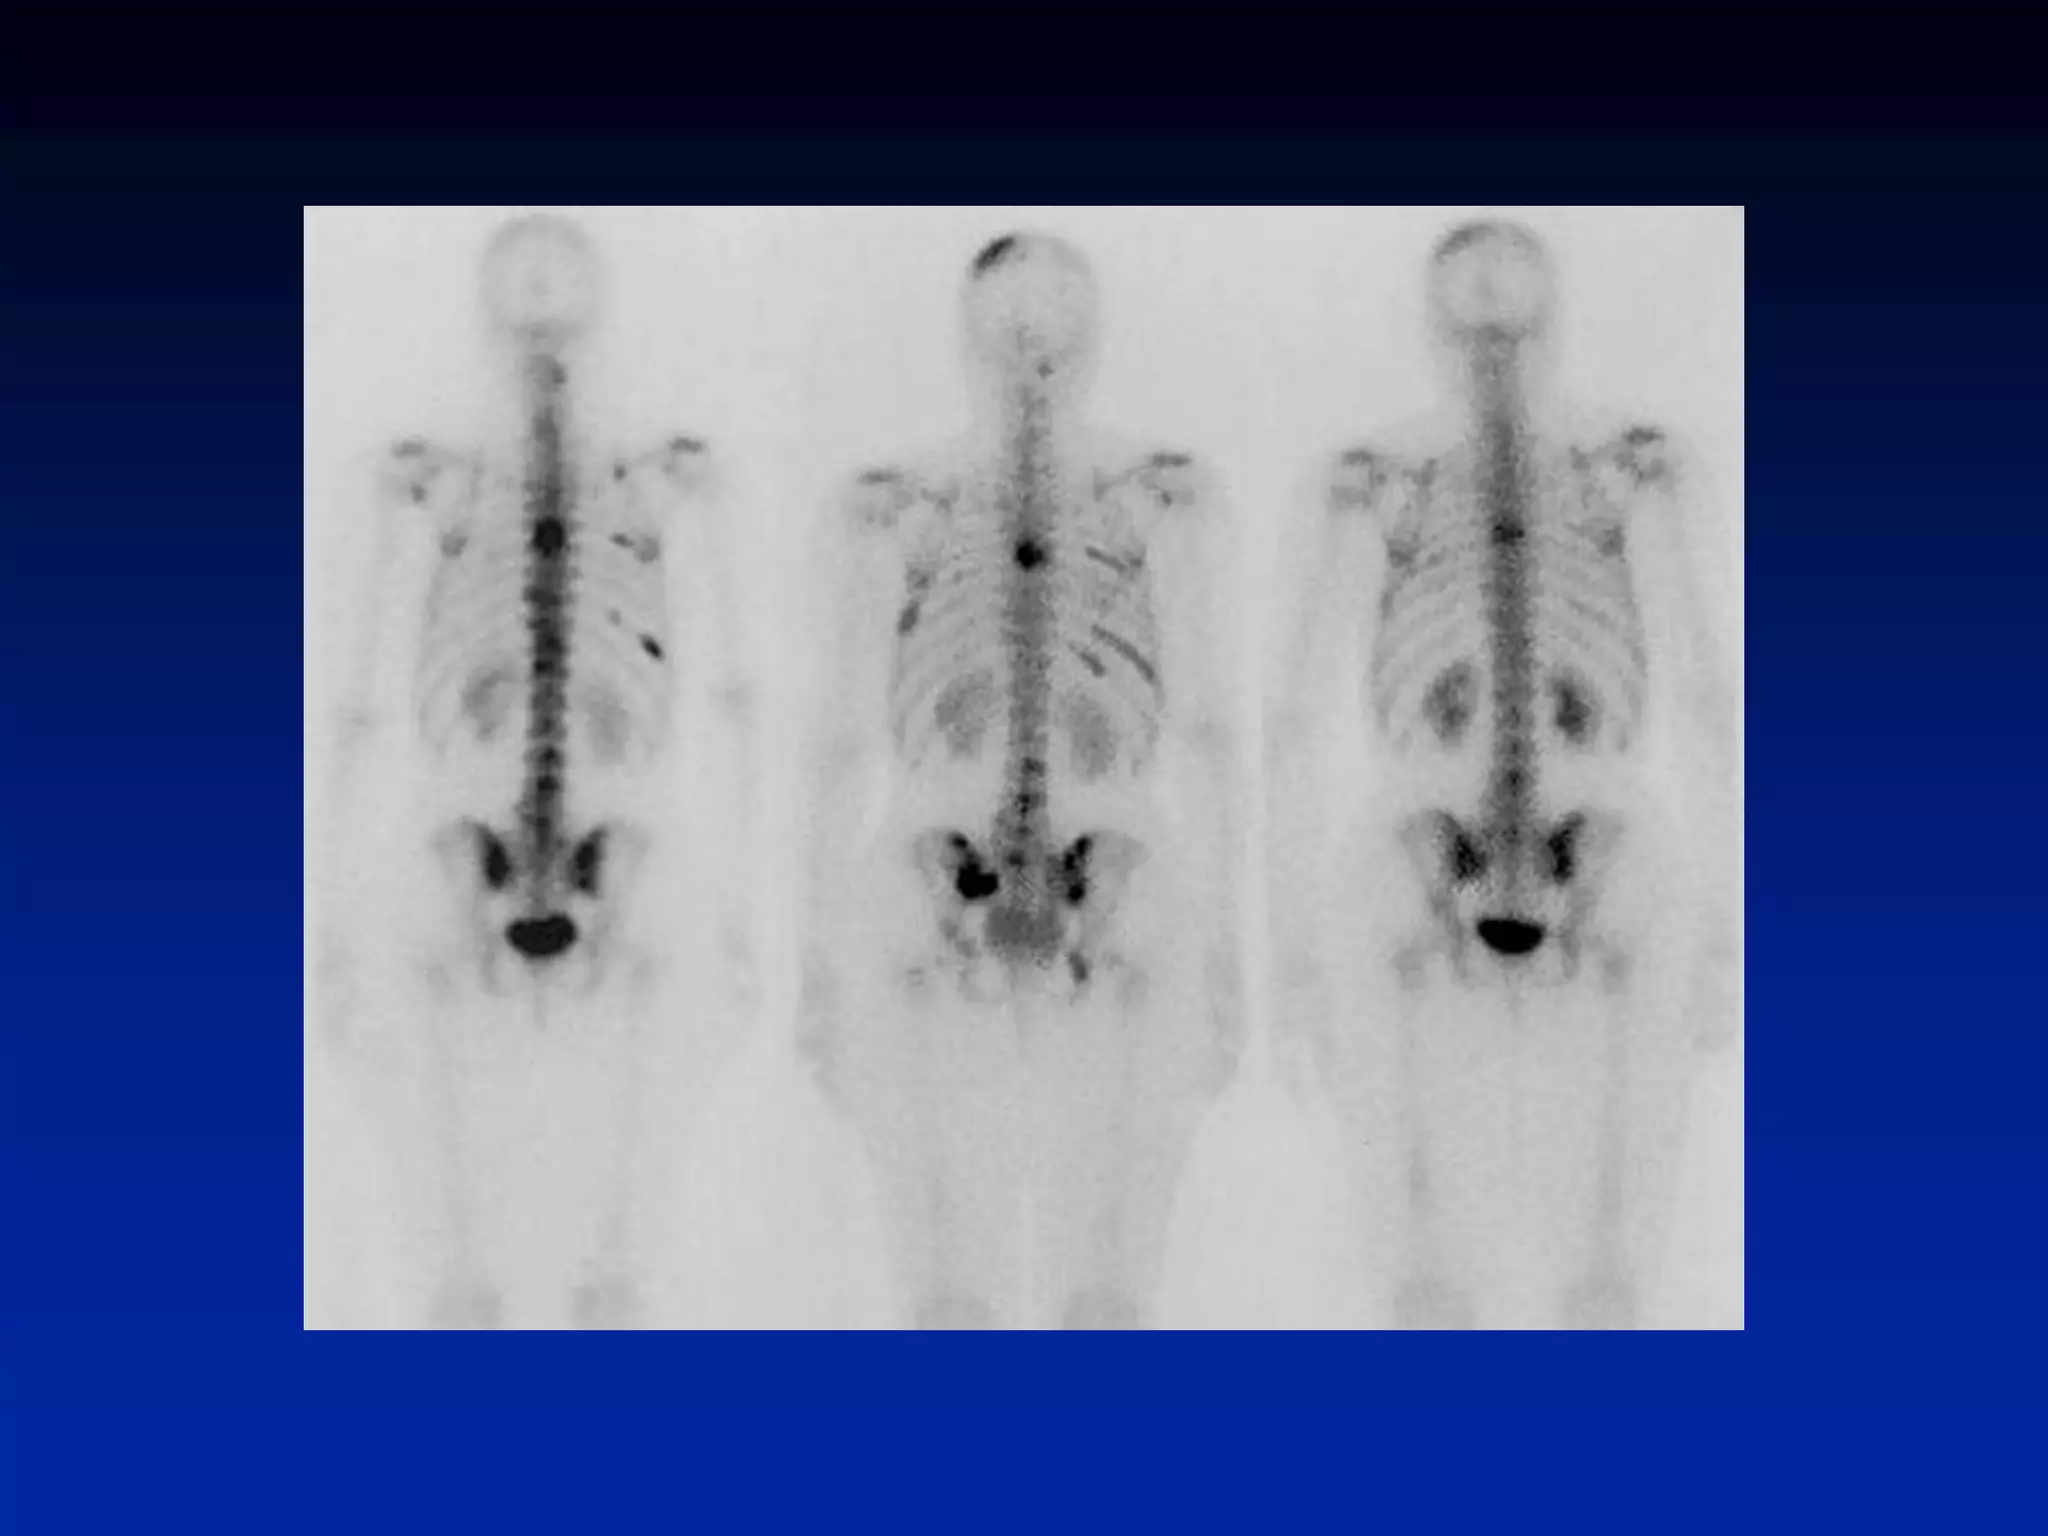

Metastatic Bone Disease

Prostate Cancer

• The presence of multiple, randomly

distributed areas of increased uptake of

varying size, shape, and intensity is highly

suggestive of bone metastases

• Though encountered in other pathologic

conditions, it is often possible to distinguish

metastatic disease from other entities by

analyzing the pattern of distribution of the

abnormalities.

• The presenceof multiple, randomly distributed areas of increased uptake of varying size, shape, and intensity is highly suggestive of bone metastases • Though encountered in other pathologic conditions, it is often possible to distinguish metastatic disease from other entities by analyzing the pattern of distribution of the abnormalities. • Metastatic disease occasionally manifests as a solitary abnormality, usually in the spine like in degenerative d/s. SPECT is